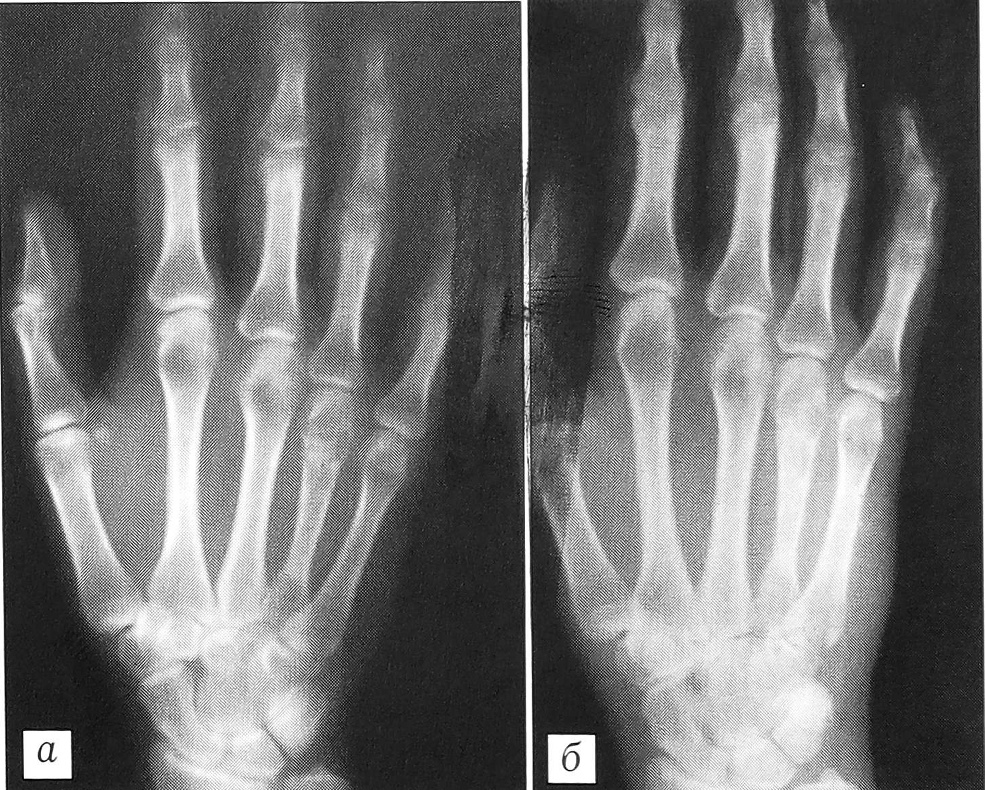

Анализ рентгенограмм показал, что через 1 мес после хирургических вмешательств картина неоднородной «глыбчатой» структуры в местах заполнения дефектов «Остеоматриксом» или в пространствах между его гранулами и аллоимплантатами, выявлявшаяся сразу после операции, полностью исчезала. Рентгеновская тень была практически однородной и имела умеренную плотность (рис. 1). Через 3 мес в большинстве случаев (66%), а через 6 мес у всех больных места, куда помещался «Остеоматрикс», по плотности рентгеновского изображения были неотличимы от окружающей губчатой костной ткани (рис. 2). Признаки перестройки замороженных кортикальных аллоимплантатов, применявшихся совместно с гранулами «Остеоматрикса», во все сроки наблюдения были минимальными (рис. 3), тогда как поверхностно-деминерализованные кортикальные аллотрансплантаты к 6-му месяцу частично инкорпорировались в материнское костное ложе (рис. 4).

Рис. 4. Рентгенограммы больной С. 21 года. Диагноз: гигантоклеточная опухоль большеберцовой кости.a — до операции; б — через 5 мес после операции с пластикой дефекта «Остеоматриксом» и «Перфоостом».

Рис. 5. Рентгенограммы больной К. 51 года. Диагноз: хондрома III пястной кости.а — до операции; б — после операции с пластикой дефекта «Остеоматриксом»; в — через 1 мес; г — через 5 мес.